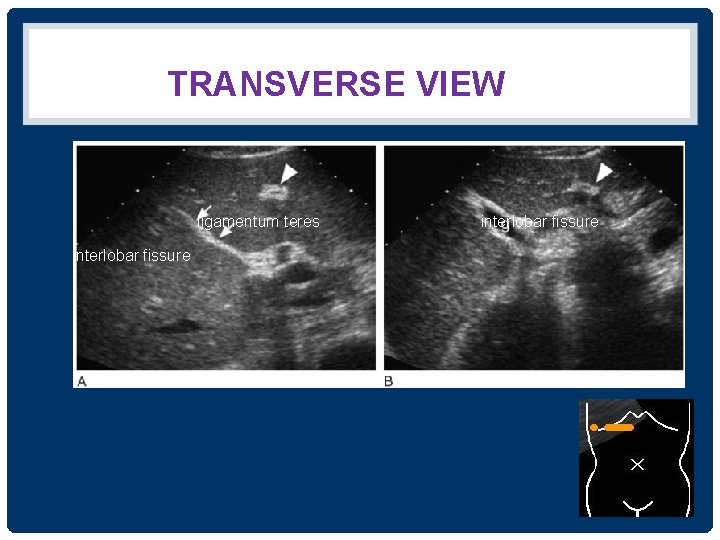

THE GALLBLADDER • อยใต interlobar fissure • ใชเปน landmark for identifying the junction between the left and right lobes of the liver • งดนำงดอาหาร ประมาณ 4 -6 ชวโมง adequate gallbladder distention + reduce upper abdominal bowel gas

TRANSVERSE VIEW ligamentum teres interlobar fissure